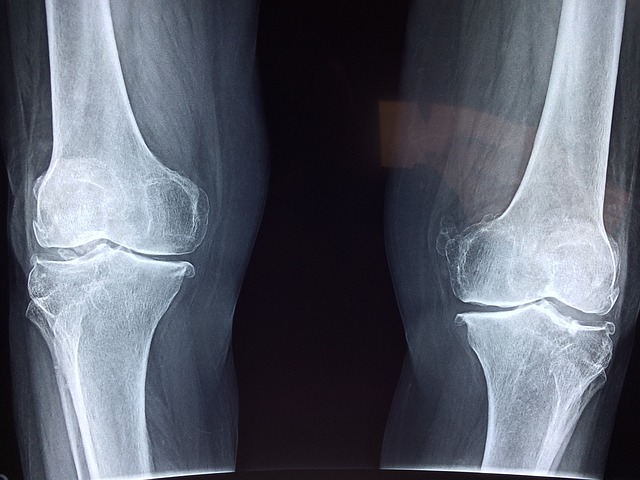

-X선, MRI, 초음파 등을 통해 관절의 상태를 확인합니다.

X선, MRI 등을 통해 관절의 상태를 확인합니다.